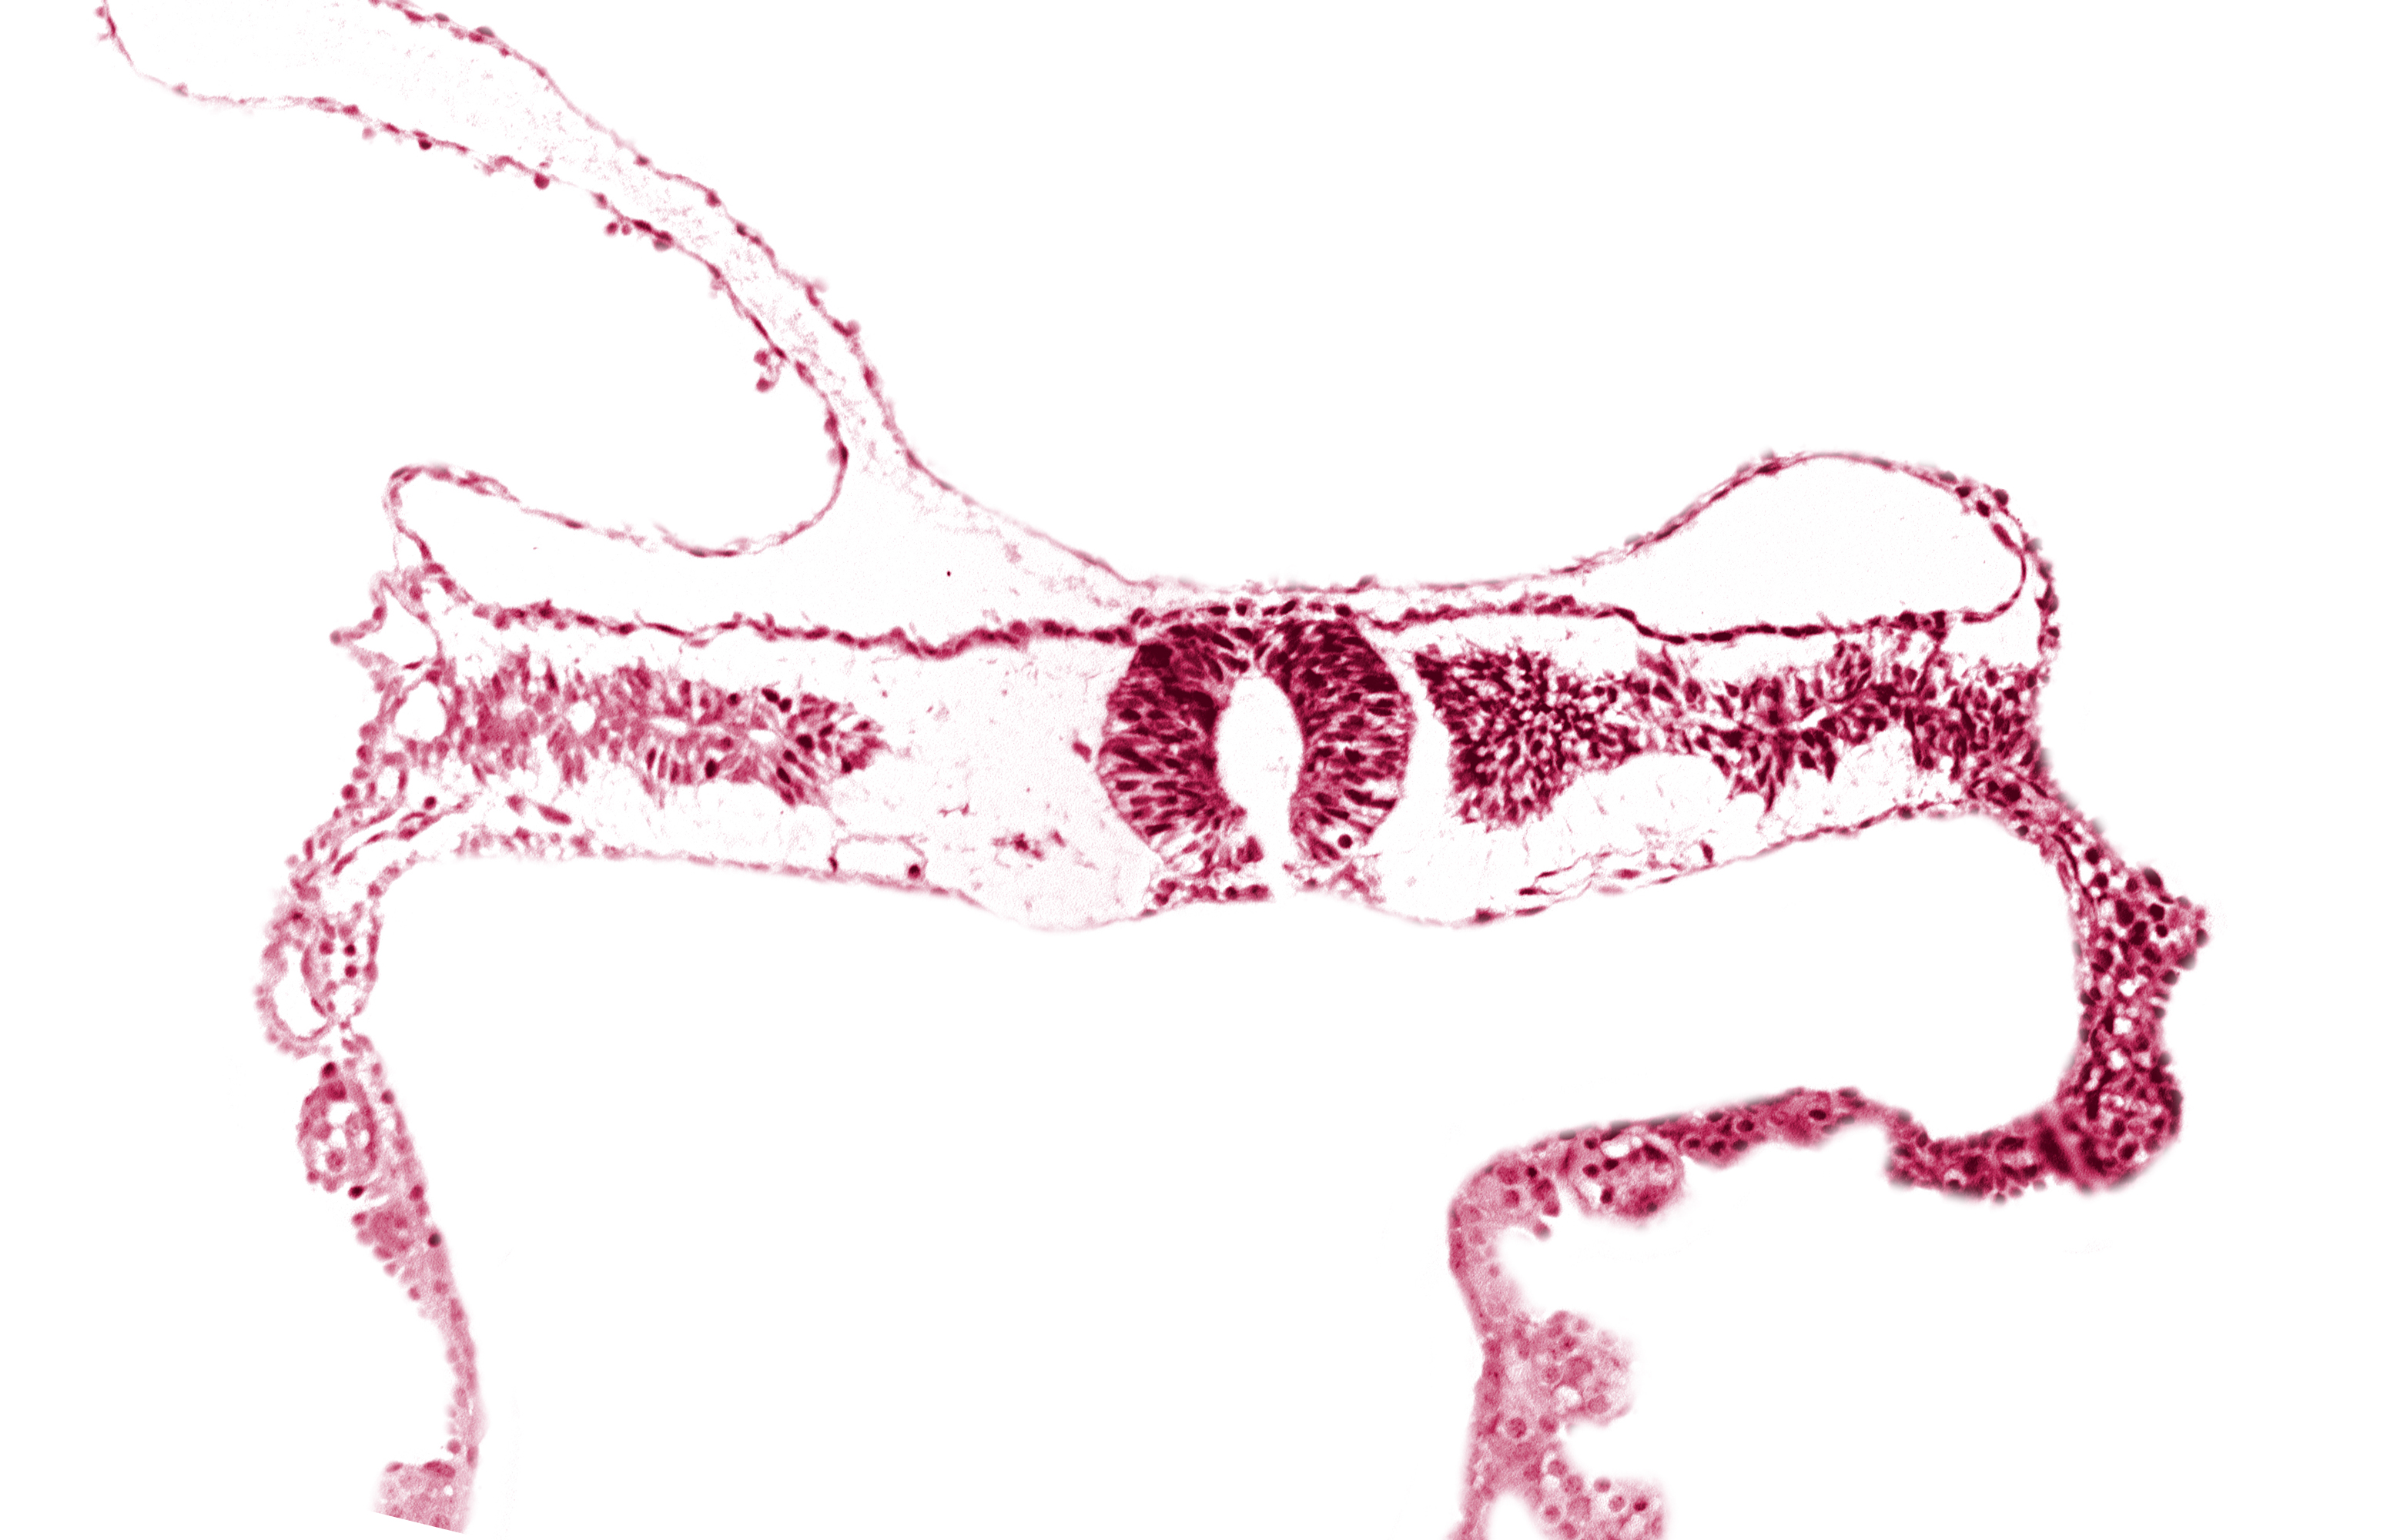

Keywords: midgut, neural tube [rhombencephalon (Rh. D)], somite 3-4 intersegmental region